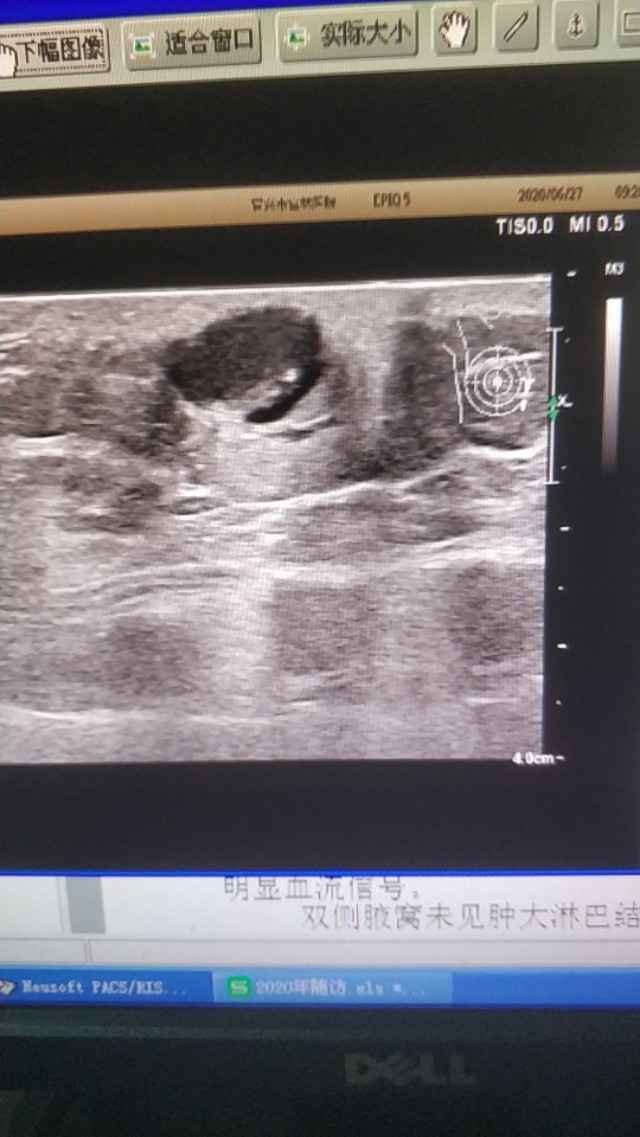

上图是一个左膝部的表皮囊肿,与皮肤真皮层关系密切,里面回声细密伴裂隙样低回声。

(这两个病例是上个月随访的)